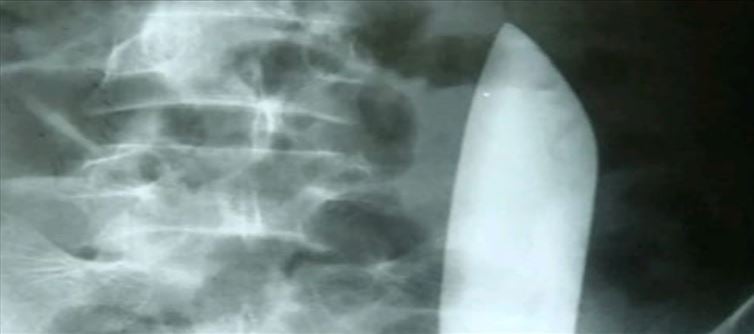

ఖాట్మండులో ఒక డాక్టర్ నిర్వాకం ఏకంగా 22 ఏళ్ళ యువకుడి ప్రాణాల మీదికి తీసుకువచ్చింది. ఇంతకీ ఏం జరిగిందంటే.. ఒక ఘర్షణలో కత్తిపోటు గాయాల పాలైన వ్యక్తిని ఇక కుటుంబ సభ్యులు ఆసుపత్రికి తీసుకువెళ్లారు. అయితే డాక్టర్ కుట్లు వేసి ఇంటికి పంపించాడు. దీంతో ప్రాణాపాయం తప్పింది అని అందరూ ఊపిరి పీల్చుకున్నారు. కానీ కొన్ని గంటలకు మళ్ళీ నొప్పి పెరగడంతో మరో ఆసుపత్రికి తీసుకువెళ్లారు. అయితే స్కానింగ్ చేసి చూడక ఏకంగా ఆ యువకుడు కడుపులో 15 సెంటీమీటర్ల పొడవైన కత్తి ఉండడంతోఅందరూ షాక్ అయ్యారు. ఇక డాక్టర్లు మళ్ళీ సర్జరీ చేసి కడుపులో ఉన్న కత్తిని బయటకు తీశారు.